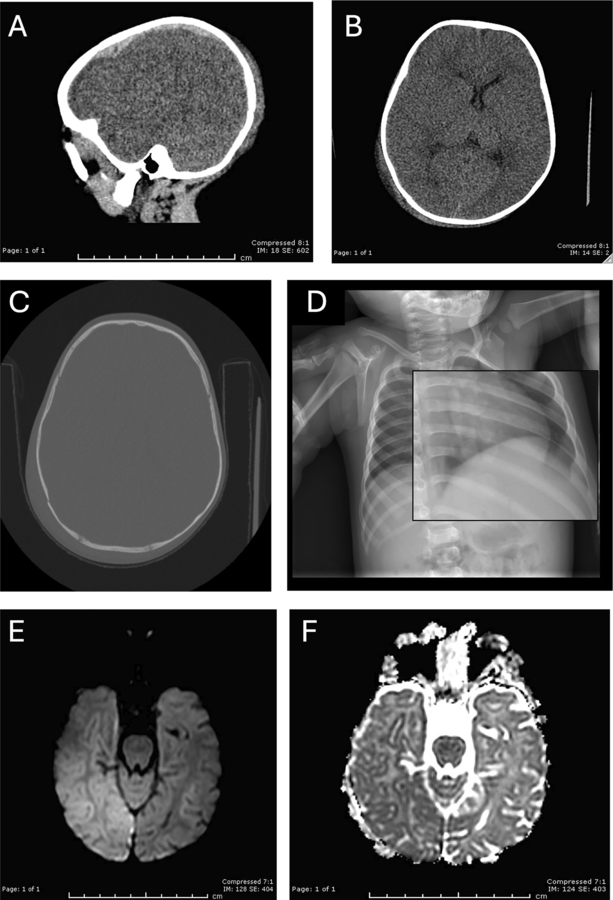

In this retrospective analysis of 479 pediatric patients who underwent skeletal surveys between 2019 and 2020, 10.5% before and 11.6% during the pandemic showed high suspicion for CPA—indicating no significant change in overall abuse rates. However, the proportion of intracranial hemorrhage dropped from 59% to 25%, and retinal hemorrhage from 38% to just 5% during the pandemic. All retinal hemorrhage cases were accompanied by brain trauma and occurred only before the pandemic. Meanwhile, skeletal fracture patterns, demographic variables, and mortality remained unchanged. These findings point to a potential shift in how abusive injuries were inflicted or detected, rather than a reduction in abuse itself.

The study reviewed electronic medical records of children who underwent skeletal surveys for suspected CPA at a California children's hospital between January 2019 and December 2020. Researchers compared demographic data and injury types—including brain hemorrhages, fractures, and bruises—before and after March 19, 2020, when California's stay-at-home order began. Statistical tests such as Pearson's chi-square and Fisher's exact were used to identify significant differences in injury patterns across time periods.